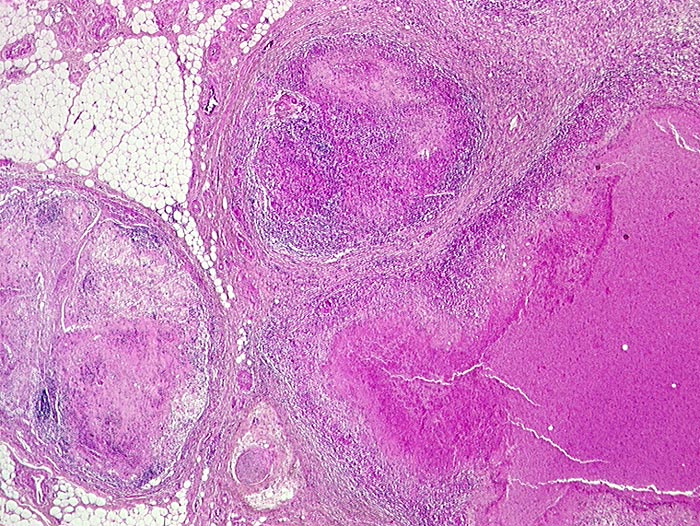

Atypische Mycobakteriose

Lymphknoten, abdominal

Ausgedehnte käsige Nekroseherde in mesenterialen Lymphknoten.

Nachweis von säurefesten Stäbchen (Mycobakterium avium intracellulare) in den Nekrosen.

AIDS. HIV Positivität bekannt seit 2 Jahren bei iv Drogenabusus.